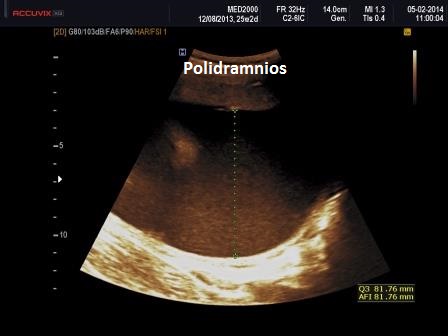

6) polidramnios.